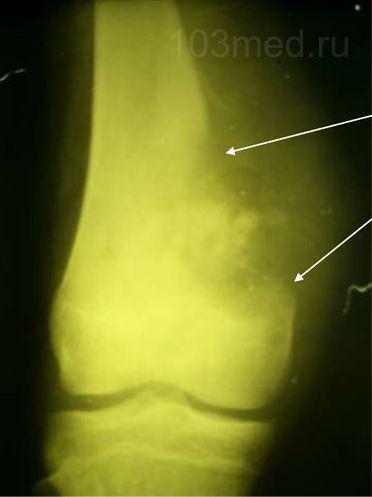

Фото 2. Вид тазовых костей на рентгене

Более доступный и бесконтактный метод это рентген. Однако он выявляет лишь зрелую вторичную метастазу, когда разрушению уже подвергся значительный объем кости. Преимущество рентгенологии заключается возможности дифференцирования вторичного новообразования, исходя из его типа. Разная окраска пятен на фото, будет говорить о различной их природе.

Что же касается рентгенологического исследования, то начальные стадии появления метастазов не дадут достаточное количество информации. Определить размер очага и его точную локализацию в костях становится возможным только тогда, когда метастатическое образование созреет, а это происходит тогда, когда костная масса разрушена уже наполовину.

Рентгенологическое исследование метастазов в кости дает возможность дифференцировать типы метастазов при диагностировании. Наличие темных пятен (разрыхленные зоны), которые имеет серо-белая костная ткань, свидетельствует о пребывании литических метастазов. При белых пятнах на снимках, которые по тону несколько светлее костной ткани (при плотной или склеротической области) можно делать заключение, что имеем дело с бластическими метастазами.

Более доступный и бесконтактный метод это рентген . Однако он выявляет лишь зрелую вторичную метастазу, когда разрушению уже подвергся значительный объем кости. Преимущество рентгенологии заключается возможности дифференцирования вторичного новообразования, исходя из его типа. Разная окраска пятен на фото, будет говорить о различной их природе.